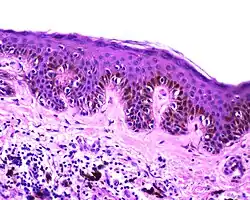

Blue nevus | It is blue in color as its melanocytes are very deep in the skin. | ![]() |

![]() |